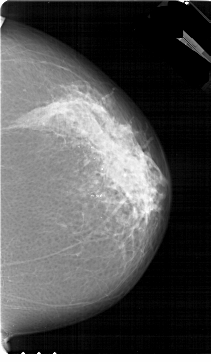

A_1774_1.RIGHT_MLO

RIGHT_MLO LINES 6871 PIXELS_PER_LINE 4141 BITS_PER_PIXEL 12 RESOLUTION 43.5 NON_OVERLAY